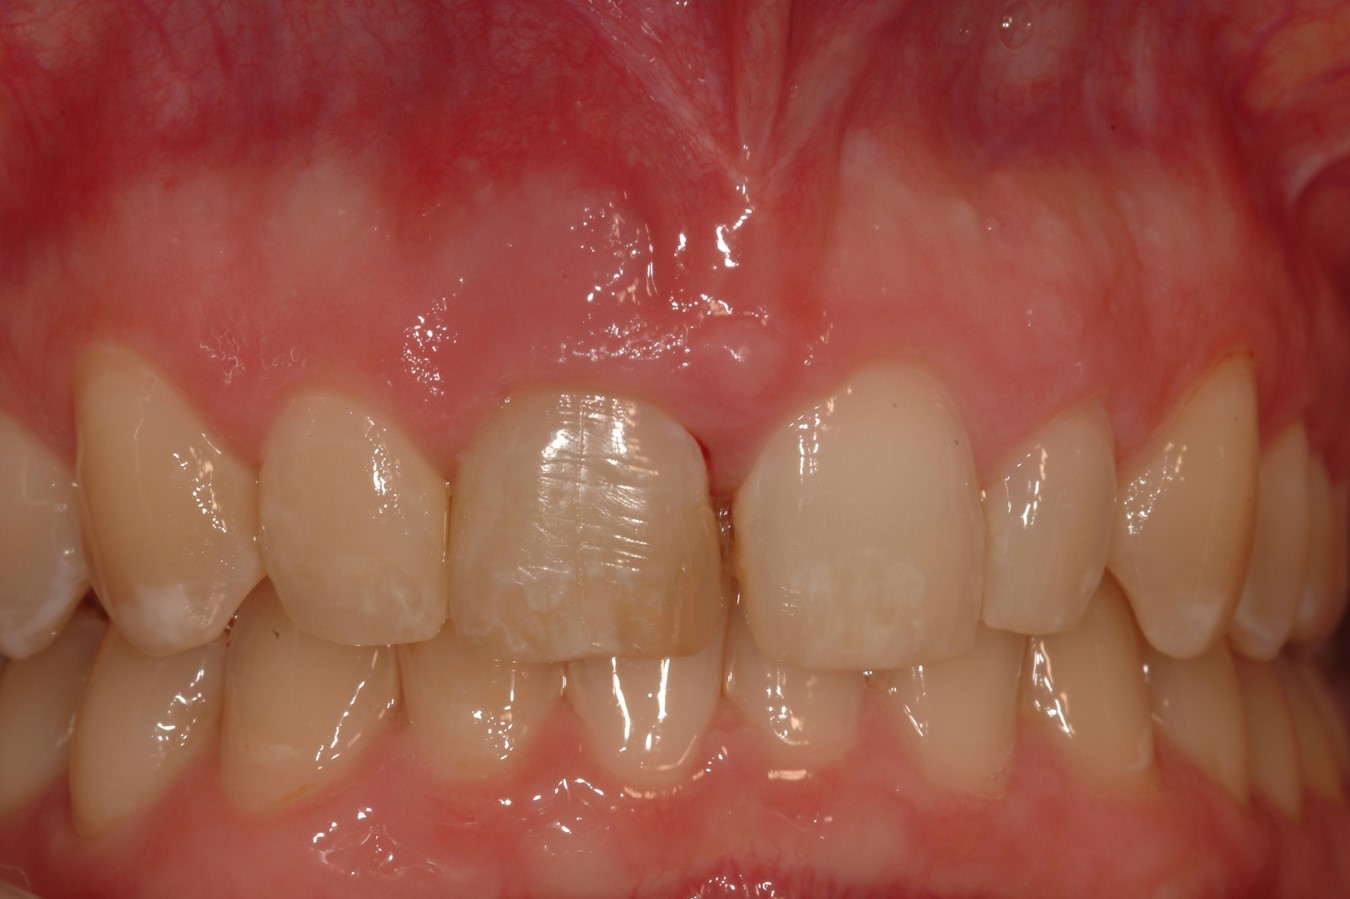

Fig 13. Case 2: Close-up retracted preoperative view of a patient who presented with a worn crown and post that had been removed and re-cemented several times.

Figure 13

A patient presented with a worn crown and post that had been removed and re-cemented several times (Figure 13 and Figure 14). Among the approaches that could have been considered was an extensive procedure to include extraction, implant placement, bone grafting, and soft-tissue grafting simultaneously.

However, by giving consideration to the most appropriate and minimally invasive sequence of care, this led to performing predictable procedures beginning with a tunneling procedure with a small connective tissue graft (Figure 15). Once the connective tissue graft healed (Figure 16), extra soft tissue with a thickened biotype was available. This would enable minimally invasive extraction using piezosurgery—without damaging the soft tissues (Figure 17)—followed by immediate implant placement according to 3D implant treatment planning (Figure 18 through Figure 20).